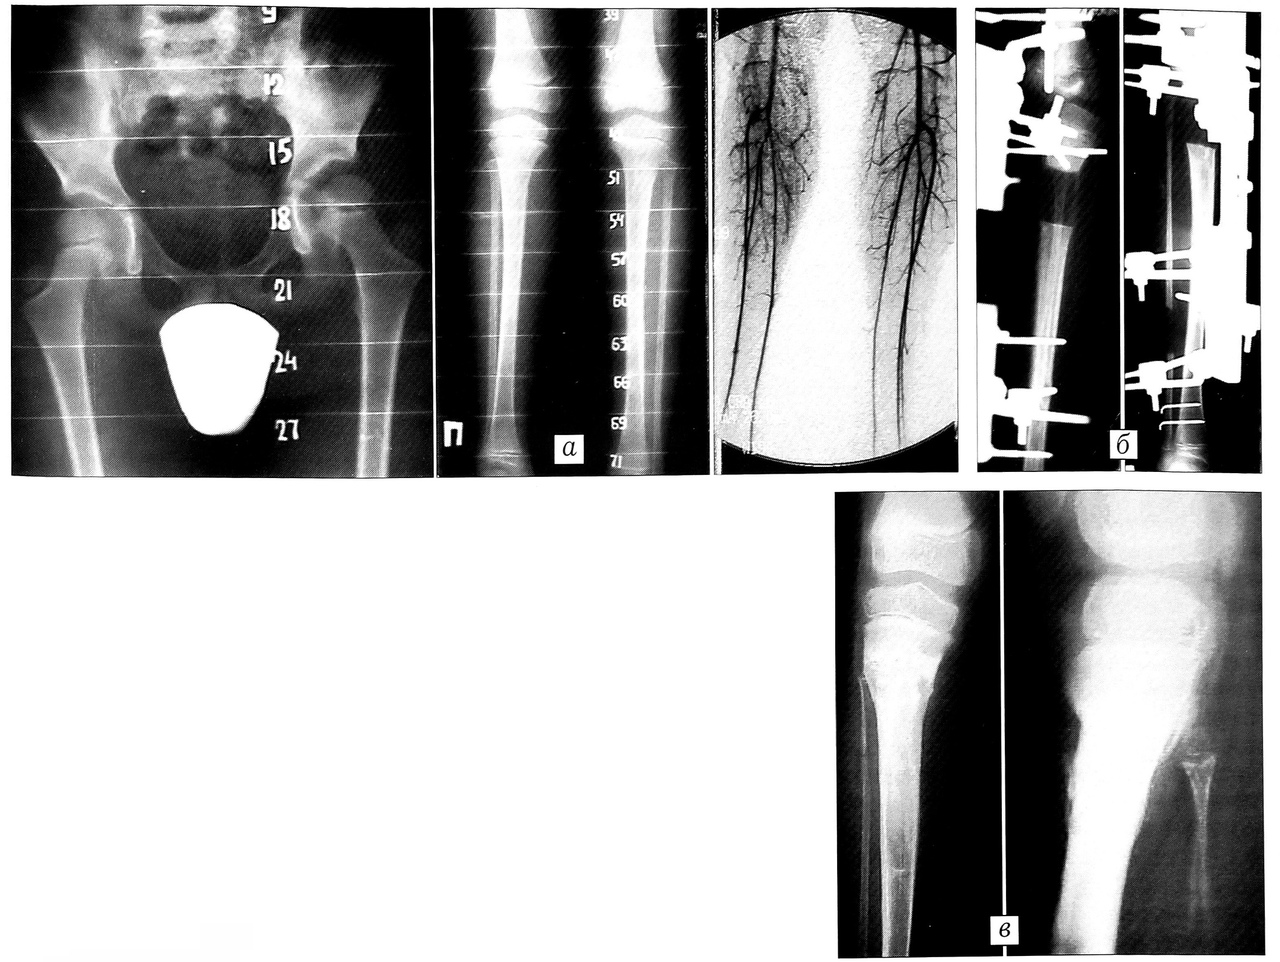

Больная В., 12 лет, диагноз: врожденное укорочение голени на 6 см, перекос таза, латеропозиция надколенника, нарушение осанки (рис. 2). Произведена остеотомия голени, наложен стержневой дистракционный аппарат. В процессе удлинения проводились активные занятия ЛФК, физиотерапия. Через 5 мес рентгенологически определяется зрелый костный регенерат. На компьютерных томограммах кортикальный слой, костномозговой канал восстановлены, нарушений целости костной трубки нет, однако толщина коркового слоя составляет 60% от таковой на контралатеральной конечности. В связи с этим после демонтажа аппарата рекомендовано в течение 2 мес во время ходьбы пользоваться ортезом.

Рис. 2. Больная В. 12 лет. Диагноз: врожденное укорочение голени на 6 см, перекос таза, латеропозиция надколенника, нарушение осанки. a — внешний вид при поступлении; б — произведена остеотомия голени, наложен стержневой дистракционный аппарат; в — в процессе удлинения’ г — через 5 мес: рентгенологически зрелый костный регенерат; д — на компьютерных томограммах кортикальный слой, костномозговой канал восстановлены, нарушений целости костной трубки нет, однако толщина коркового слоя составляет 60% от таковой на противоположной стороне.

Рис. 5. Рентгенограммы и ангиограмма больнго Г. 8 лет. Диагноз: врожденное укорочение правой голени на 6 см.а — До операции (на ангиограмме — гипоплазия сосудистой сети голени); б — через 2 мес после операции: слабость дистракционного регенерата. Пункционно в область регенерата введена биоактивная полимерная «соломка» с лиофилизатом ЭКТ; в — через 6 мес после операции.

Больной Г., 8 лет, диагноз: врожденное укорочение правой голени (рис. 5). Произведена остеотомия большеберцовой кости в верхней трети, наложен стержневой дистракционный аппарат. Через 2 мес после начала удлинения отмечена слабость дистракционного регенерата. Пункционно в область регенерата введена биоактивная полимерная «соломка» с лиофилизатом ЭКТ. Через 6 мес после операции состояние регенерата позволило демонтировать аппарат.